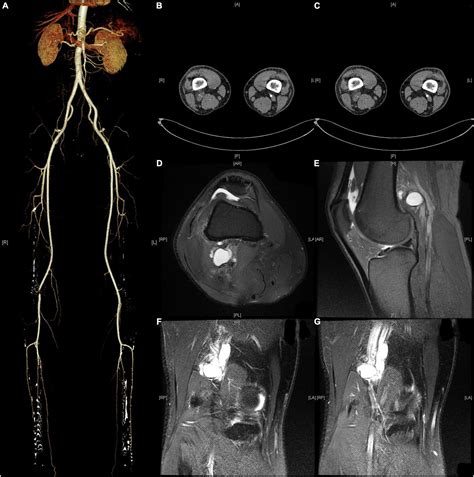

• Imaging Studies: Imaging tests such as ultrasound, magnetic resonance imaging (MRI), or computed tomography (CT) angiography can help visualize the popliteal artery and surrounding structures. These tests can identify any compression or entrapment of the artery.

• Angiography: In some cases, an angiogram may be performed to directly visualize the blood vessels and assess the extent of the entrapment.